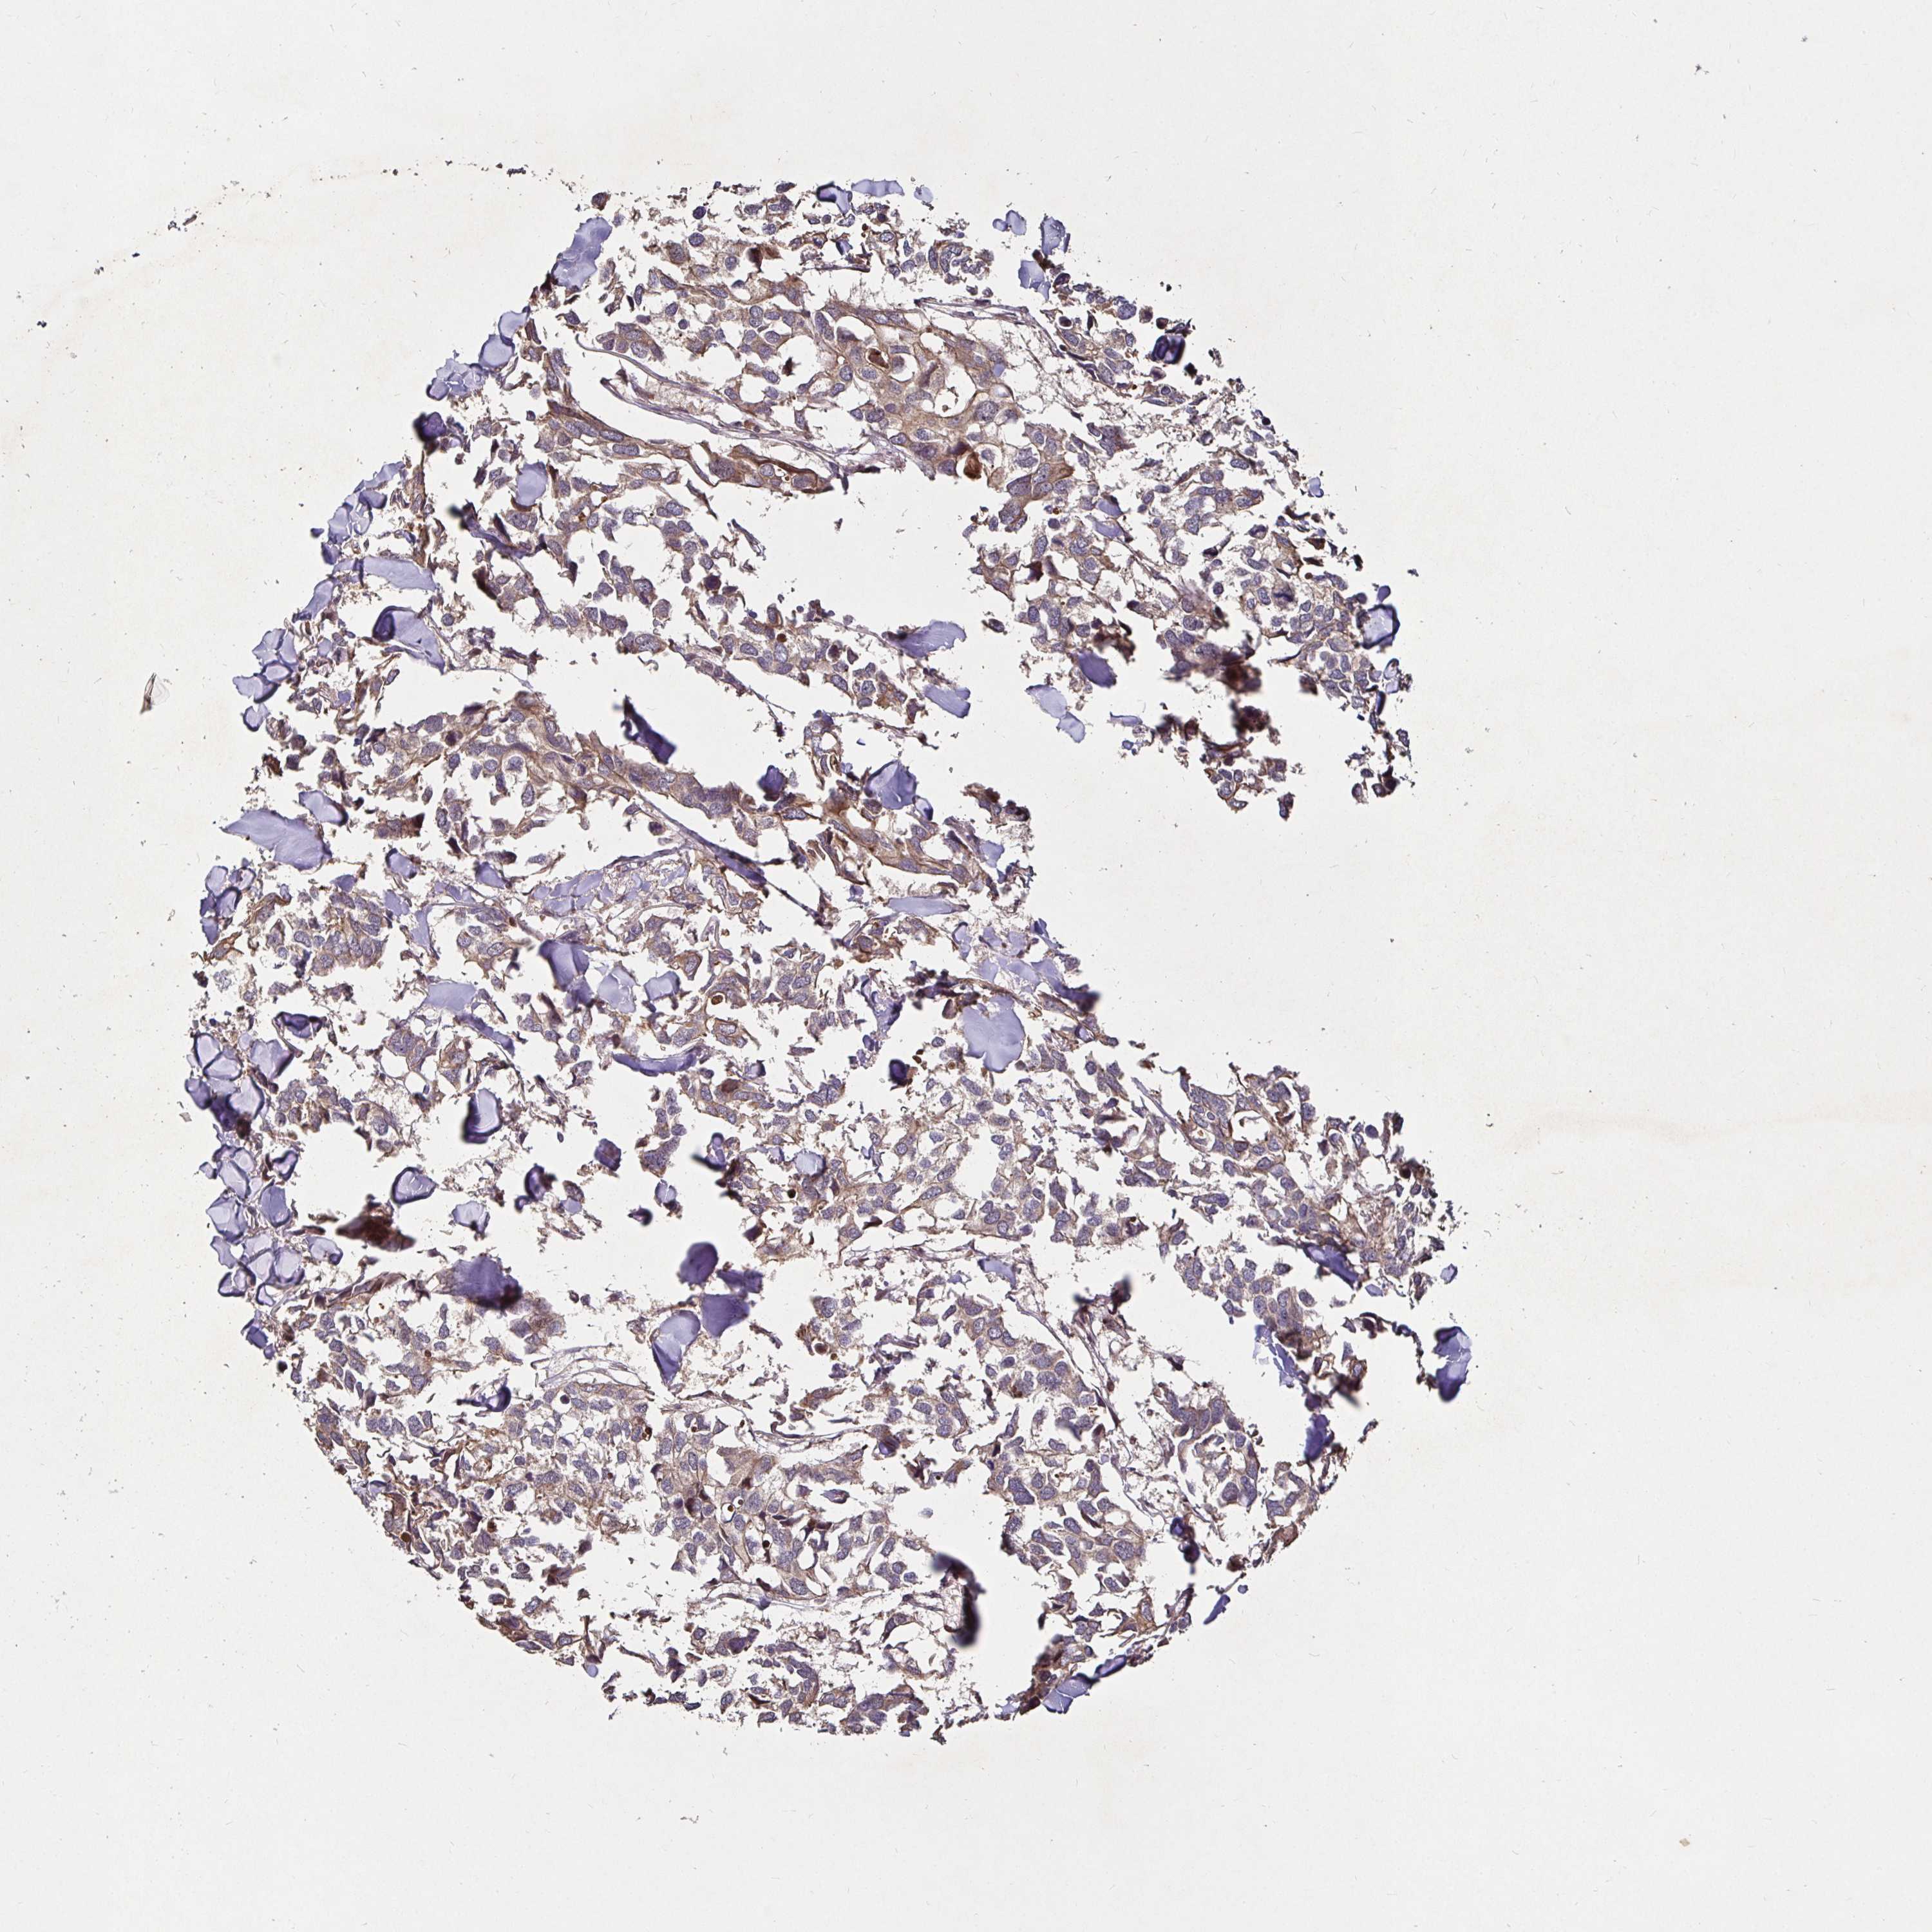

CANCER BREAST CANCER Show tissue menu

BRCA TCGA BRCA VALIDATION PROTEIN EXPRESSION